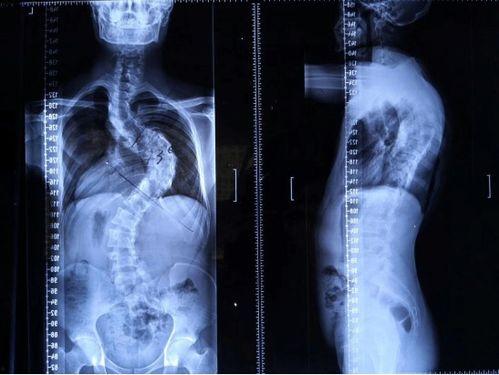

脊柱矫正,顾名思义,就是通过各种方法来调整脊柱的形态,使其恢复到正常状态。这个过程可能涉及到物理治疗、按摩、针灸、手术等多种手段。那么,成人还能矫正脊柱吗?答案是肯定的!

脊柱矫正的原理其实很简单,就是通过外力来改变脊柱的受力点,从而逐步调整脊柱的形态。这个过程需要耐心和毅力,因为脊柱矫正并非一蹴而就的事情。